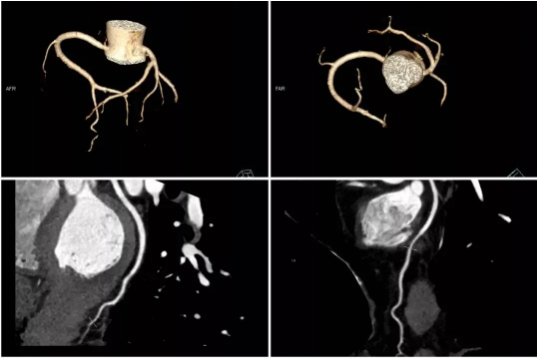

CTA是CT血管造影的英文缩写,冠状动脉CTA就是应用静脉注射造影剂,通过螺旋CT(一般64排或以上效果为好)对冠状动脉血管成像,观察冠状动脉的情况的一种检查方法。